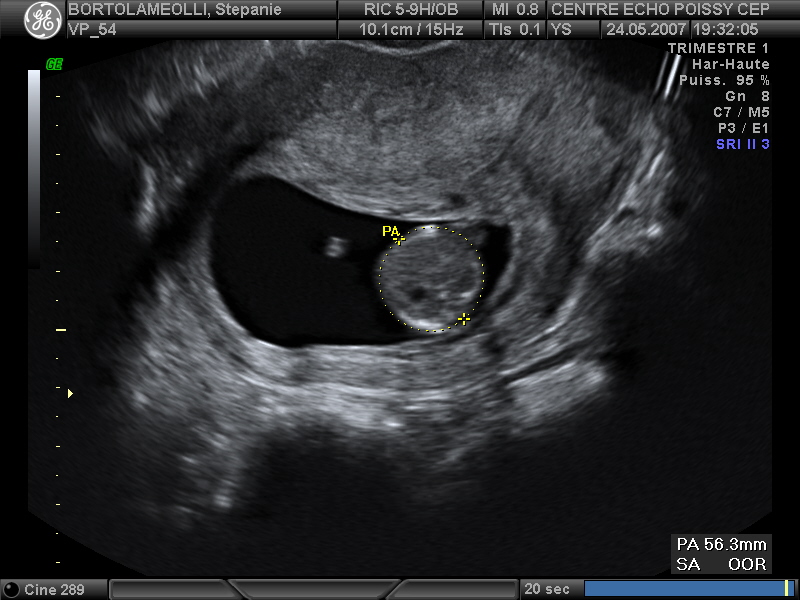

Echographies

Mai 2007